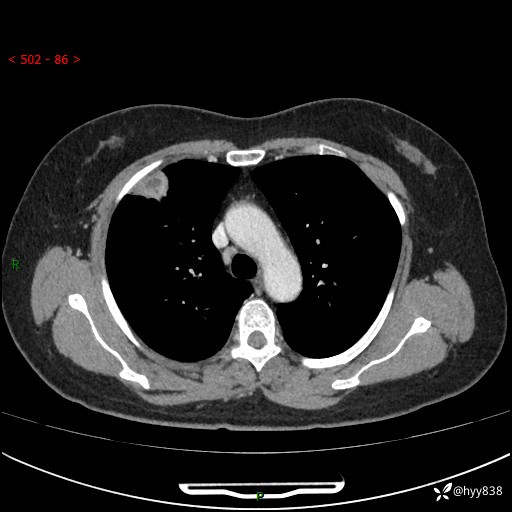

现病史:患者于2天余前无明显出现间断胸痛,无头痛、头晕,无心慌、胸闷、胸痛、呼吸困难、低热、盗汗,无腹痛、腹胀等不适,未进行进一步诊治。于2024.04.14在当地市人民医院行胸部CT检查提示:右肺上叶胸膜下结节。现患者为求进一步诊治,来我院就诊。以“肺肿物”收入我科。 患者自起病以来,精神可,睡眠可,饮食可,大小便正常,体重无明显改变。

胸部CT增强(肺窗,外院平扫)